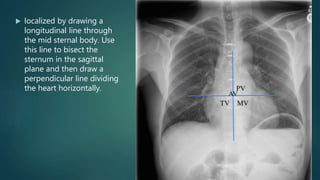

 localized by drawing a

longitudinal line through

the mid sternal body. Use

this line to bisect the

sternum in the sagittal

plane and then draw a

perpendicular line dividing

the heart horizontally.

 localized bydrawing a longitudinal line through the mid sternal body. Use this line to bisect the sternum in the sagittal plane and then draw a perpendicular line dividing the heart horizontally.

• #24 The location of the cardiac valves is best determined on the lateral radiograph. A line is drawn on the lateral radiograph from the carina to the cardiac apex. The pulmonic and aortic valves generally sit above this line and the tricuspid and mitral valves sit below this line